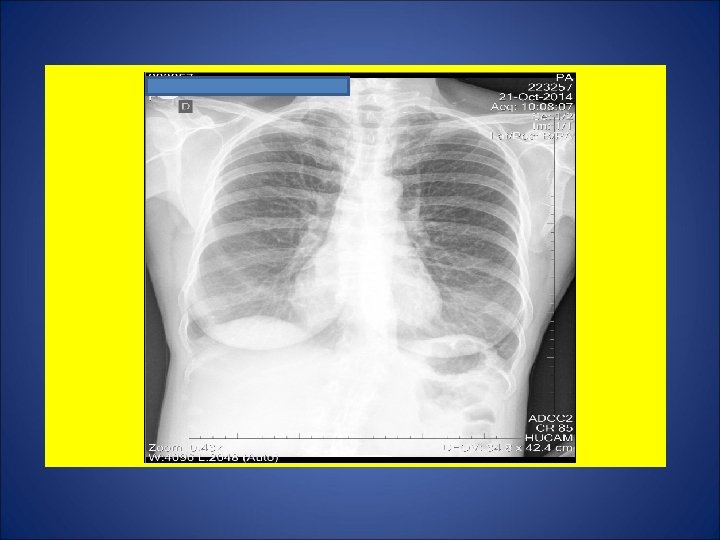

CASO 3, feminina, 25 anos de idade, agente administrativa numa creche. Tosse discreta não produtiva durante os dois últimos meses. Há 1 mês, adinamia. Há 1 semana, febre e sudorese. Durante os últimos 15 dias, perda de 5 Kg. Na madrugada de 09 julho 2014, acordou com tosse seguida de vários episódios de hemoptise. Avaliada por um otorrinolaringologista, sendo prescrito antibiótico 1 cp/dia por 5 dias. Remissão gradual da hemoptise durante os próximos dias. Persistência de tosse discreta. A partir de 21 set 14, surgimento de dor de garganta e disfonia. Negou episódios de escarros hemoptóicos ou hemoptise. A partir de 8 out 14, recidiva da tosse seguida de vários episódios de hemoptise. Foi referenciada para pneumologista, sendo solicitado radiografia de tórax e pesquisa de bacilos álcool ácido resistentes. Negou contato com casos de tuberculose. Negou tuberculose prévia. Negou tabagismo e etilismo. HIV negativa. Ex. fisico: P=73 Kg, Altura= 1, 63 m, IMC= 27, 47, FC = 110 bpm. Tem marca de BCG em MSD.

ESCARROS ESPONT NEOS: 1º) 17/10/14: 10 m. L – MUCOPURULENTO – 10 min: BAC 1+ – CULT em curso 2º) 20/10/14: 10 m. L – SALIVA – 20 min: BAC NEG – TRM M. tuberculosis - CULT em curso 3º) 20/10/14: 10 m. L – SALIVA – 15 min: BAC 2+ – CULT em curso 4º) 21/10/14: 12 m. L – MUCOPURULENTO – 30 min: BAC NEG – CULT em curso